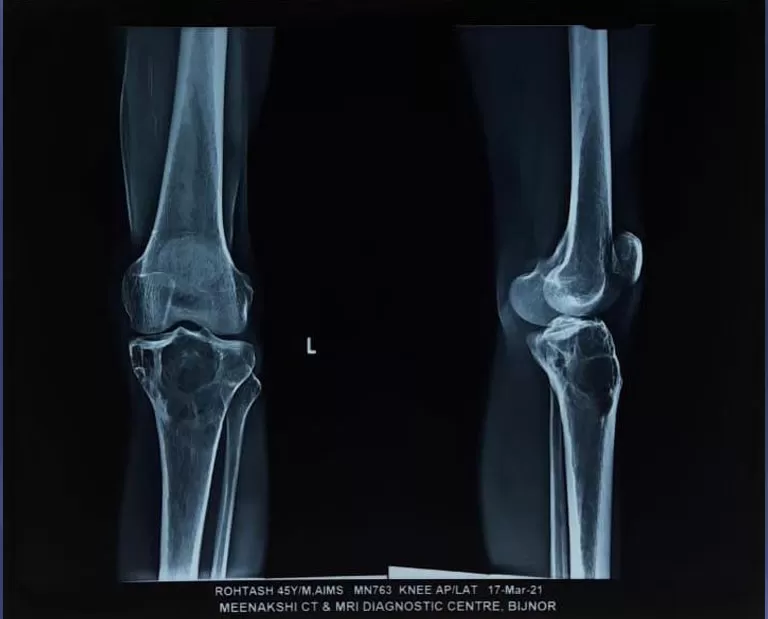

Mr. Rohtash

Name: Mr. Rohtash

Date of Operation: 17 Mar 2021

Age: 45 Years

Mobile No: 98885 35038